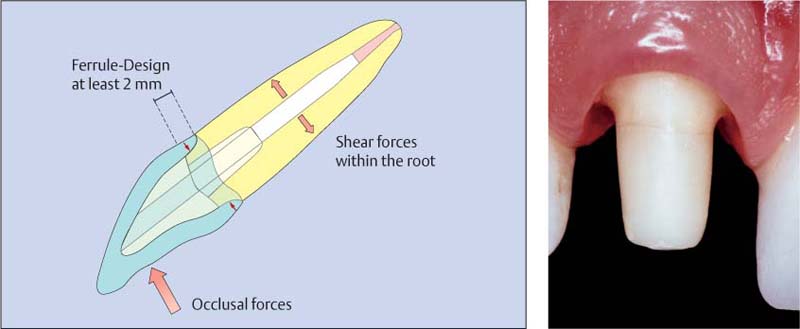

Культя зуба это

Культя зуба это 106 фото